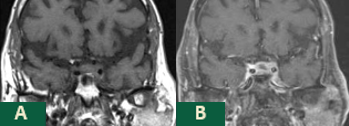

Case Presentation: A 75-year-old male presented to our institution with lethargy and unremitting headache of several weeks duration. His history was significant for squamous cell carcinoma of the lung status post lobectomy with recurrence 4 years later being treated with palliative radiation, chronic obstructive pulmonary disease (COPD), and hypertension. He described his headache as daily, aching, non-radiating retroorbital pain that progressively worsened over several weeks and did not respond to Butalbital/Acetaminophen/Caffeine and oxycodone. Pain was not exacerbated by light, sound, or eye movement. MRI of the brain 1 month prior was negative for metastases. On examination, vitals were normal. The patient was somnolent but oriented x 3 and able to answer all questions appropriately. Initial neurological examination was unremarkable. However, serial neurological examinations revealed progressively worsening left ptosis and dysconjugate gaze with preserved visual fields. Laboratory studies were significant for hyponatremia, hypocortisolemia, hypothyroidism and low follicle stimulating hormone (FSH) and testosterone levels consistent with panhypopituitarism. Repeat MRI of the brain with pituitary protocol was consistent with metastases to the anterior pituitary and infundibulum with extension into the left cavernous sinus. Treatment was initiated with steroids and thyroid replacement with improvement in the patient’s lethargy and hyponatremia. His headache was minimally improved with intravenous hydromorphone but did improve with the addition of valproic acid and gabapentin. Neurosurgery performed transphenoidal biopsy with debulking with histology confirming metastatic squamous cell carcinoma of the lung. He tolerated surgery well but continued to have persistent headaches. Repeat MRI of the brain two weeks following surgery revealed mild progression of disease in the pituitary and infundibulum, which will be treated with adjuvant radiation.

Discussion: This case is an example of an unusual presentation of metastatic squamous cell carcinoma of the lung to the pituitary gland highlighted by isolated anterior involvement with panhypopituitarism, rapid progression, and persistent, refractory retroorbital pain. There should remain high clinical suspicion for patients with known malignancy who develop similar symptoms to those seen in our patient despite recent negative imaging due to the rapidity of disease progression. MRI of the brain should be ordered with pituitary protocol for optimal visualization of the pituitary gland. Control of pain secondary to pituitary metastases may be difficult with opioids alone, but anti-epileptics may provide some degree of analgesia given the neuropathic characteristics of the pain associated with these tumors.